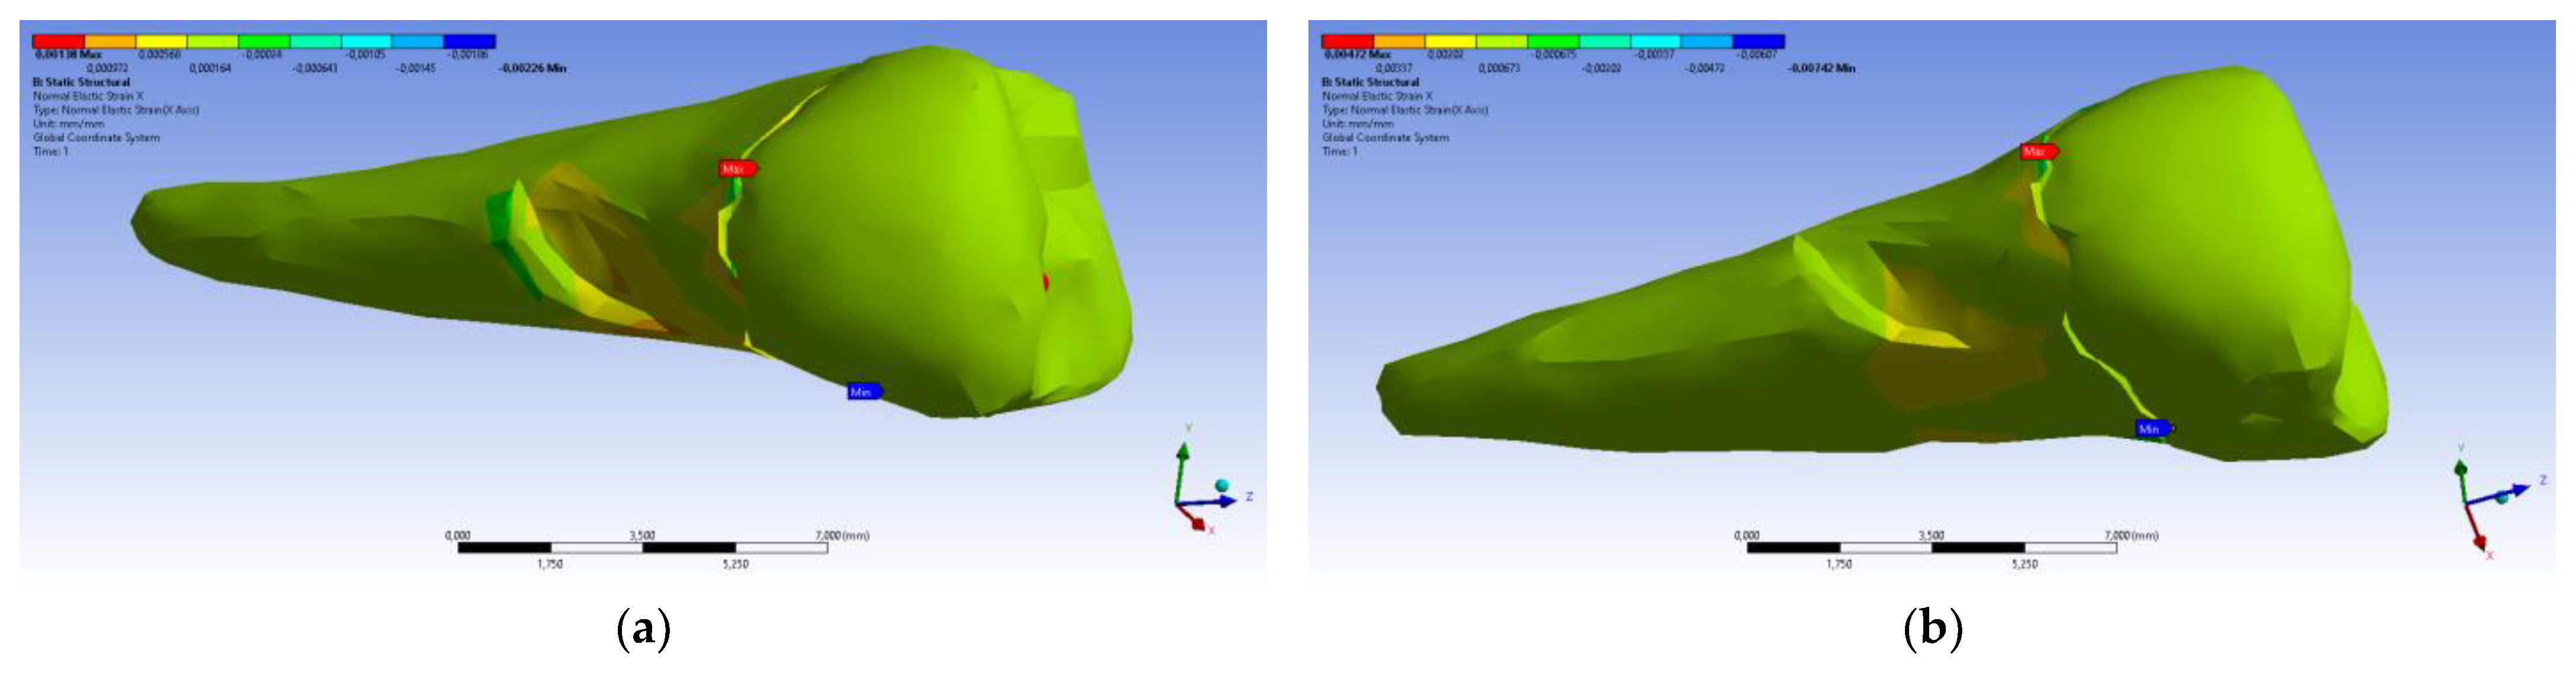

3. Finite Element Analysis (FEA) of Mandibular Right Premolars

| Maximum Tangential Stress | Main Elastic Relative Deformation | Main Maximum Elastic Relative Deformation | Main Minimum Elastic Relative Deformation | Maximum Tangential Elastic Relative Deformation | Relative elastic Normal X Deformation | Relative Elastic Normal Y Deformation | Relative Elastic Normal Z Deformation | Relative Elastic Tangential XY Deformation | Relative Elastic Tangential YZ Deformation | Relative Elastic Tangential XZ Deformation | |||

| Minimum | 5.4 × 10−7 MPa | 6.36 × 10−11 mm/mm | −1.33 × 10−5 mm/mm | −1.05 × 10−2 mm/mm | 7.6 × 10−11 mm/mm | −2.26 × 10−3 mm/mm | −1.43 × 10−3 mm/mm | −3.45 × 10−3 mm/mm | −2.81 × 10−3 mm/mm | −4.09 × 10−3 mm/mm | −7.93 × 10−3 mm/mm | ||

| Maximum | 143 MPa | 1.33 × 10−2 mm/mm | 9.66 × 10−3 mm/mm | 1.09 × 10−5 mm/mm | 2.01 × 10−2 mm/mm | 1.37 × 10−3 mm/mm | 1.89 × 10−3 mm/mm | 3.14 × 10−3 mm/mm | 6.23 × 10−3 mm/mm | 1.65 × 10−2 mm/mm | 3.13 × 10−3 mm/mm | ||

| Minim. in | Cementum | Cementum | Enamel | Cementum | Cementum | Cementum | Cementum | Cementum | Cementum | Cementum | Cementum | ||

| Maxim. in | Cementum | Cementum | Cementum | Cementum | Cementum | Cementum | Cementum | Enamel | Cementum | Cementum | Cementum |